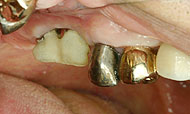

![]() ▲自然に骨結合しにくいと判断した場合、連結コーピングで動かない環境を作ってやることが重要 |

初期固定が悪く多少動揺する場合の工夫

インプラント窩の形成途中で穴の径が大きくなって初期固定が悪くなり、植立した時点で多少動揺することがある。しかし、工夫次第で3,4週間で骨結合してくることが多い。その工夫を以下にまとめてみる。